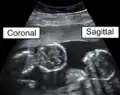

The sagittal plane (/ˈsæɪtəl/; also known as the longitudinal plane) is an anatomical plane that divides the body into right and left sections.[1] It is perpendicular to the transverse and coronal planes. The plane may be in the center of the body and divide it into two equal parts (mid-sagittal), or away from the midline and divide it into unequal parts (para-sagittal).